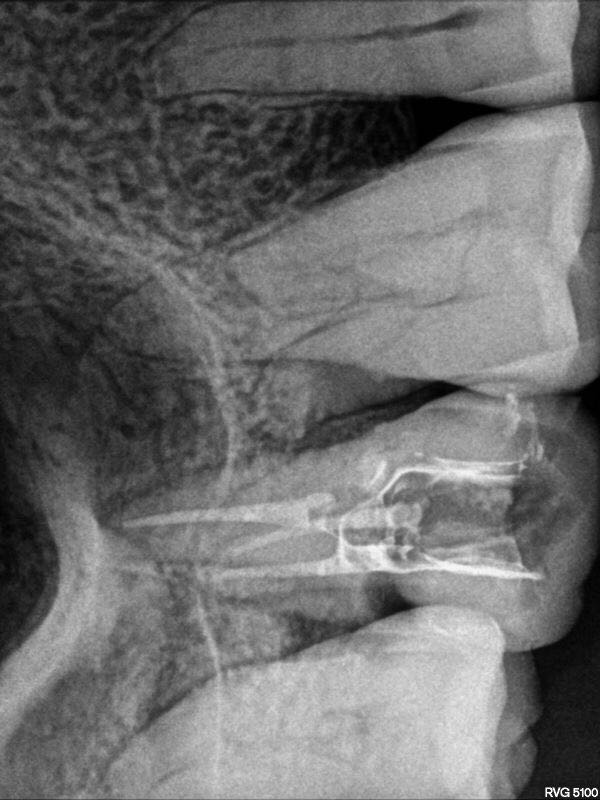

行近中壁侧穿修补,之后在显微镜下ET20暴露根管口,三根,均行疏通,扩锉根充

此病例,最大的难点就是髓石堵住根管口,导致根管异常难以进入,显微镜在复杂根管治疗这方面确实非常优秀。另外这个病例会侧穿主要还是太大意了,以为用了超声就万事大吉,慎之慎之